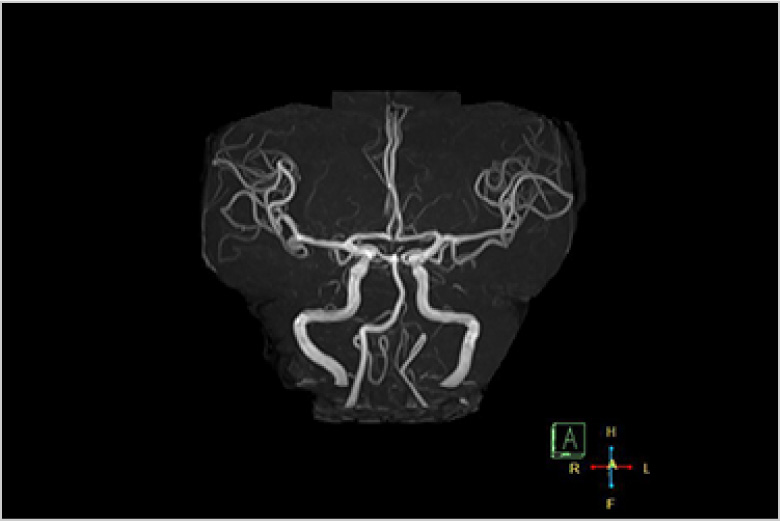

MRI(磁気共鳴画像)

MRIとは、Magnetic Resonance Imaging の略で磁気共鳴断層撮影装置と呼ばれ、強い磁場の中で、人体内の水素原子核に電波を与え、そこから発生した電波を受し画像化する検査です。

MRIは、X線撮影(一般撮影・CT)では描出できない脳・脊髄・椎間板・半月板・筋肉・腱・血管などの描出に優れています。また、人体の様々な断面像が得られるのと同時にX線を使わないため被ばくの心配がありません。

急性期の脳梗塞の診断に優れ、脳外科領域において非常に有用な検査です。軟部組織のコントラストに優れ、外科・整形外科・婦人科・泌尿器科の検査に有用です。

認知症や脳動脈瘤の診断など、検診等にも有用です。

造影剤を使用しなくても血管画像が得られる為腎機能が悪い方にも有用です。

頭部MRA